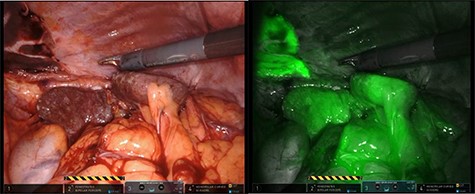

After mobilization of the left liver lobe, visualization of the hiatus was achieved. A two silk suture was placed through the avascular hepatogastric ligament and outside the patient’s anterior abdomen with an extracorporeal knot in order to assure atraumatic elevation-retraction of the liver. Space was created in the surgical field due to the absence of a retracting surgical instrument within the abdominal cavity. The hernia’s sac was then dissected with use of energy device and bipolar cautery with minimal traumatic tissue handling; the herniated stomach, transverse and left colon, omentum and finally spleen were dissected free (Fig. 2). Due to the atypical clinical symptomatology as well as increased PLT, the suspicion of chronic ischemia of the herniated organs was raised. ICG was administered to assess the patency of blood supply in the herniated organs and specially to the spleen; blood supply was excellent and as a result, no further resections were needed (Fig. 3). An 8- × 4-cm posterolateral diaphragmatic defect was revealed; the defect was repaired with the use of ProGrip mesh and was supported by a continuous V-loc suture for fixation. The patient resuscitated from anesthesia in great condition and returned to the ward, with an uneventful course. A post-operative upper GI fluoroscopy was conducted at the second post-operative day (POD), and oral diet was commenced (Fig. 4).

The use of intraoperative ICG and the use of Firefly camera to assess blood supply and viability of the spleen.